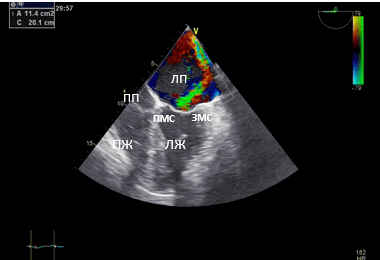

Данные интаоперационной 3D ЧП ЭхоКГ: Митральный клапан: ФК 44 мм, створки уплотнены, расщепление передней створки от свободного края до фиброзного кольца в сегменте А 2, движение створок разнонаправленное. Градиент давления максимальный — 6,2 мм рт.ст., средний 2,1 мм рт.ст. Регургитация выраженная: vena contracta - 0,9 см, площадь потока регургитации — 11,4 см², в непрерывноволновом допплеровском режиме плотный поток регургитации, радиус PISA — 1,0 см. Регургитация — эксцентричная, по боковой стенке ЛП.

Рис. 2. Чреспищеводная эхокардиография. Среднепищеводный доступ. Четырёхкамерная позиция. (ПП — правое предсердие). Площадь потока регургитации — 11,4 см².